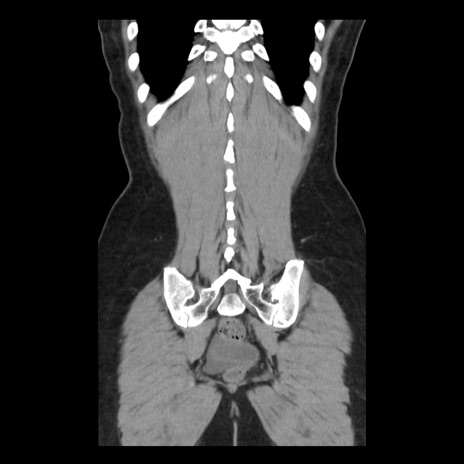

症例10(冠状断像)

【症例】 50歳代女性

【主訴】 腹痛

【現病歴】前日生レバーを食べた。今朝に排便あり。 昼前に突然発症の腹痛を生じ、当院救急外来を受診した。

【既往歴】 子宮筋腫にてで子宮全摘後

【身体所見】 意識清明、腹部:平坦、軟、下腹部やや左を中心に圧痛・反跳痛あり、筋性防御あり

【データ】WBC 7800、CRP 0.07